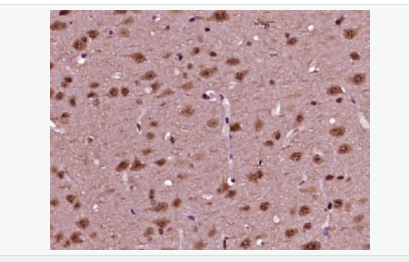

首頁>>免疫學>>一抗>>磷酸化神經細胞分化因子1抗體

磷酸化神經細胞分化因子1抗體

Rabbit anti-phospho-NeuroD1 (Ser274) Polyclonal antibody

交叉反應:Human,Mouse,Rat(predicted:Pig,Cow,Sheep) 推薦應用:WB,IHC-P,IHC-F,ICC,IF,ELISA

英文名稱phospho-NeuroD1 (Ser274)

中文名稱磷酸化神經細胞分化因子1抗體

別    名NeuroD1 (phospho S274); p-NeuroD1 (phospho S274); atonal; basic helix loop helix transcription factor; BETA 2; Beta cell E box transactivator 2; BETA2; BHF 1; BHF1; bHLHa3; class A basic helix loop helix protein 3; Class A basic helix-loop-helix protein 3; MODY 6; MODY6; NDF1_HUMAN; NEUROD; NeuroD1; Neurogenic differentiation 1; Neurogenic differentiation factor 1; neurogenic helix loop helix protein NEUROD; NIDDM.

產品類型磷酸化抗體

研究領域腫瘤  心血管  細胞生物  神經生物學  表觀遺傳學

產品應用WB=1:500-2000 ELISA=1:5000-10000 IHC-P=1:100-500 IHC-F=1:100-500 ICC=1:100-500 IF=1:100-500 (石蠟切片需做抗原修復)

免 疫 原KLH conjugated Synthesised acetylpeptide derived from human NeuroD1 around the acetylation site of Ser274:PL(p-S)PP

產品介紹This gene encodes a member of the NeuroD family of basic helix-loop-helix (bHLH) transcription factors. The protein forms heterodimers with other bHLH proteins and activates transcription of genes that contain a specific DNA sequence known as the E-box. It regulates expression of the insulin gene, and mutations in this gene result in type II diabetes mellitus. [provided by RefSeq, Jul 2008]

Differentiation factor required for dendrite morphogenesis and maintenance in the cerebellar cortex. Transcriptional activator. Binds to the insulin gene E-box.

Phosphorylated. In islet cells, phosphorylated on Ser-274 upon glucose stimulation; which may be required for nuclear localization. In activated neurons, phosphorylated on Ser-335; which promotes dendritic growth.